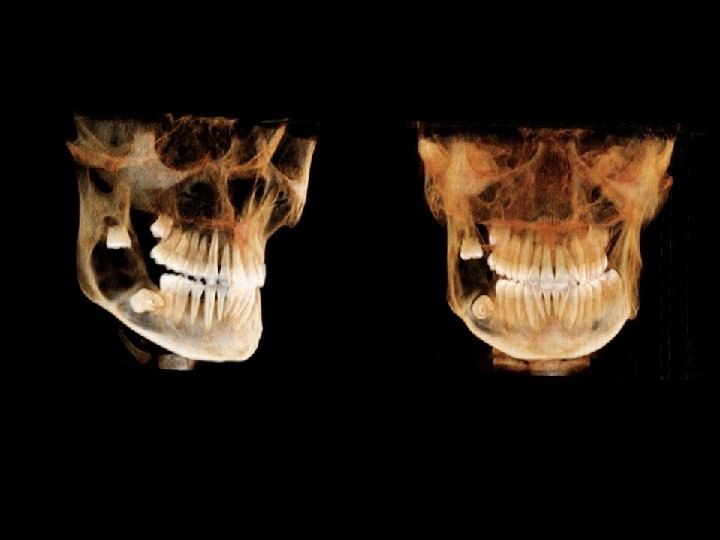

CBCT